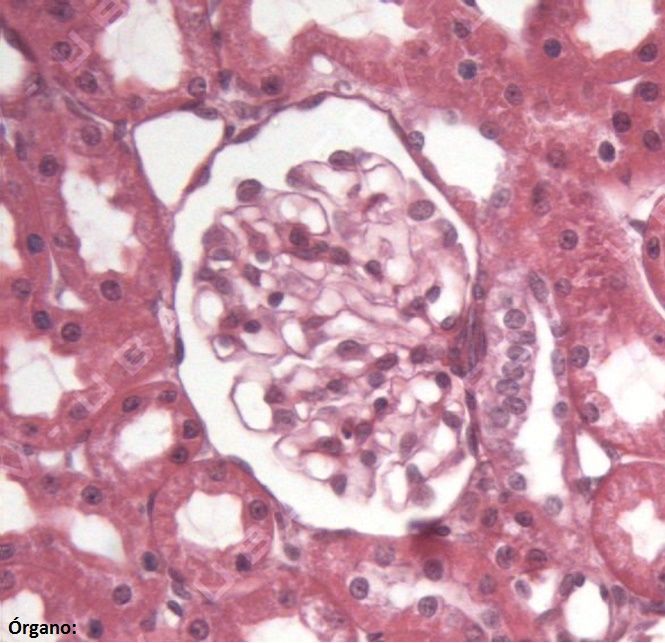

Question 1

Question

Escriba el nombre de las estructuras marcadas y del órgano (abajo a la izquierda). Nota: tenga en cuenta los acentos y las faltas de ortografía.

Answer

• Mácula densa

• Túbulo contorneado proximal

• Riñón